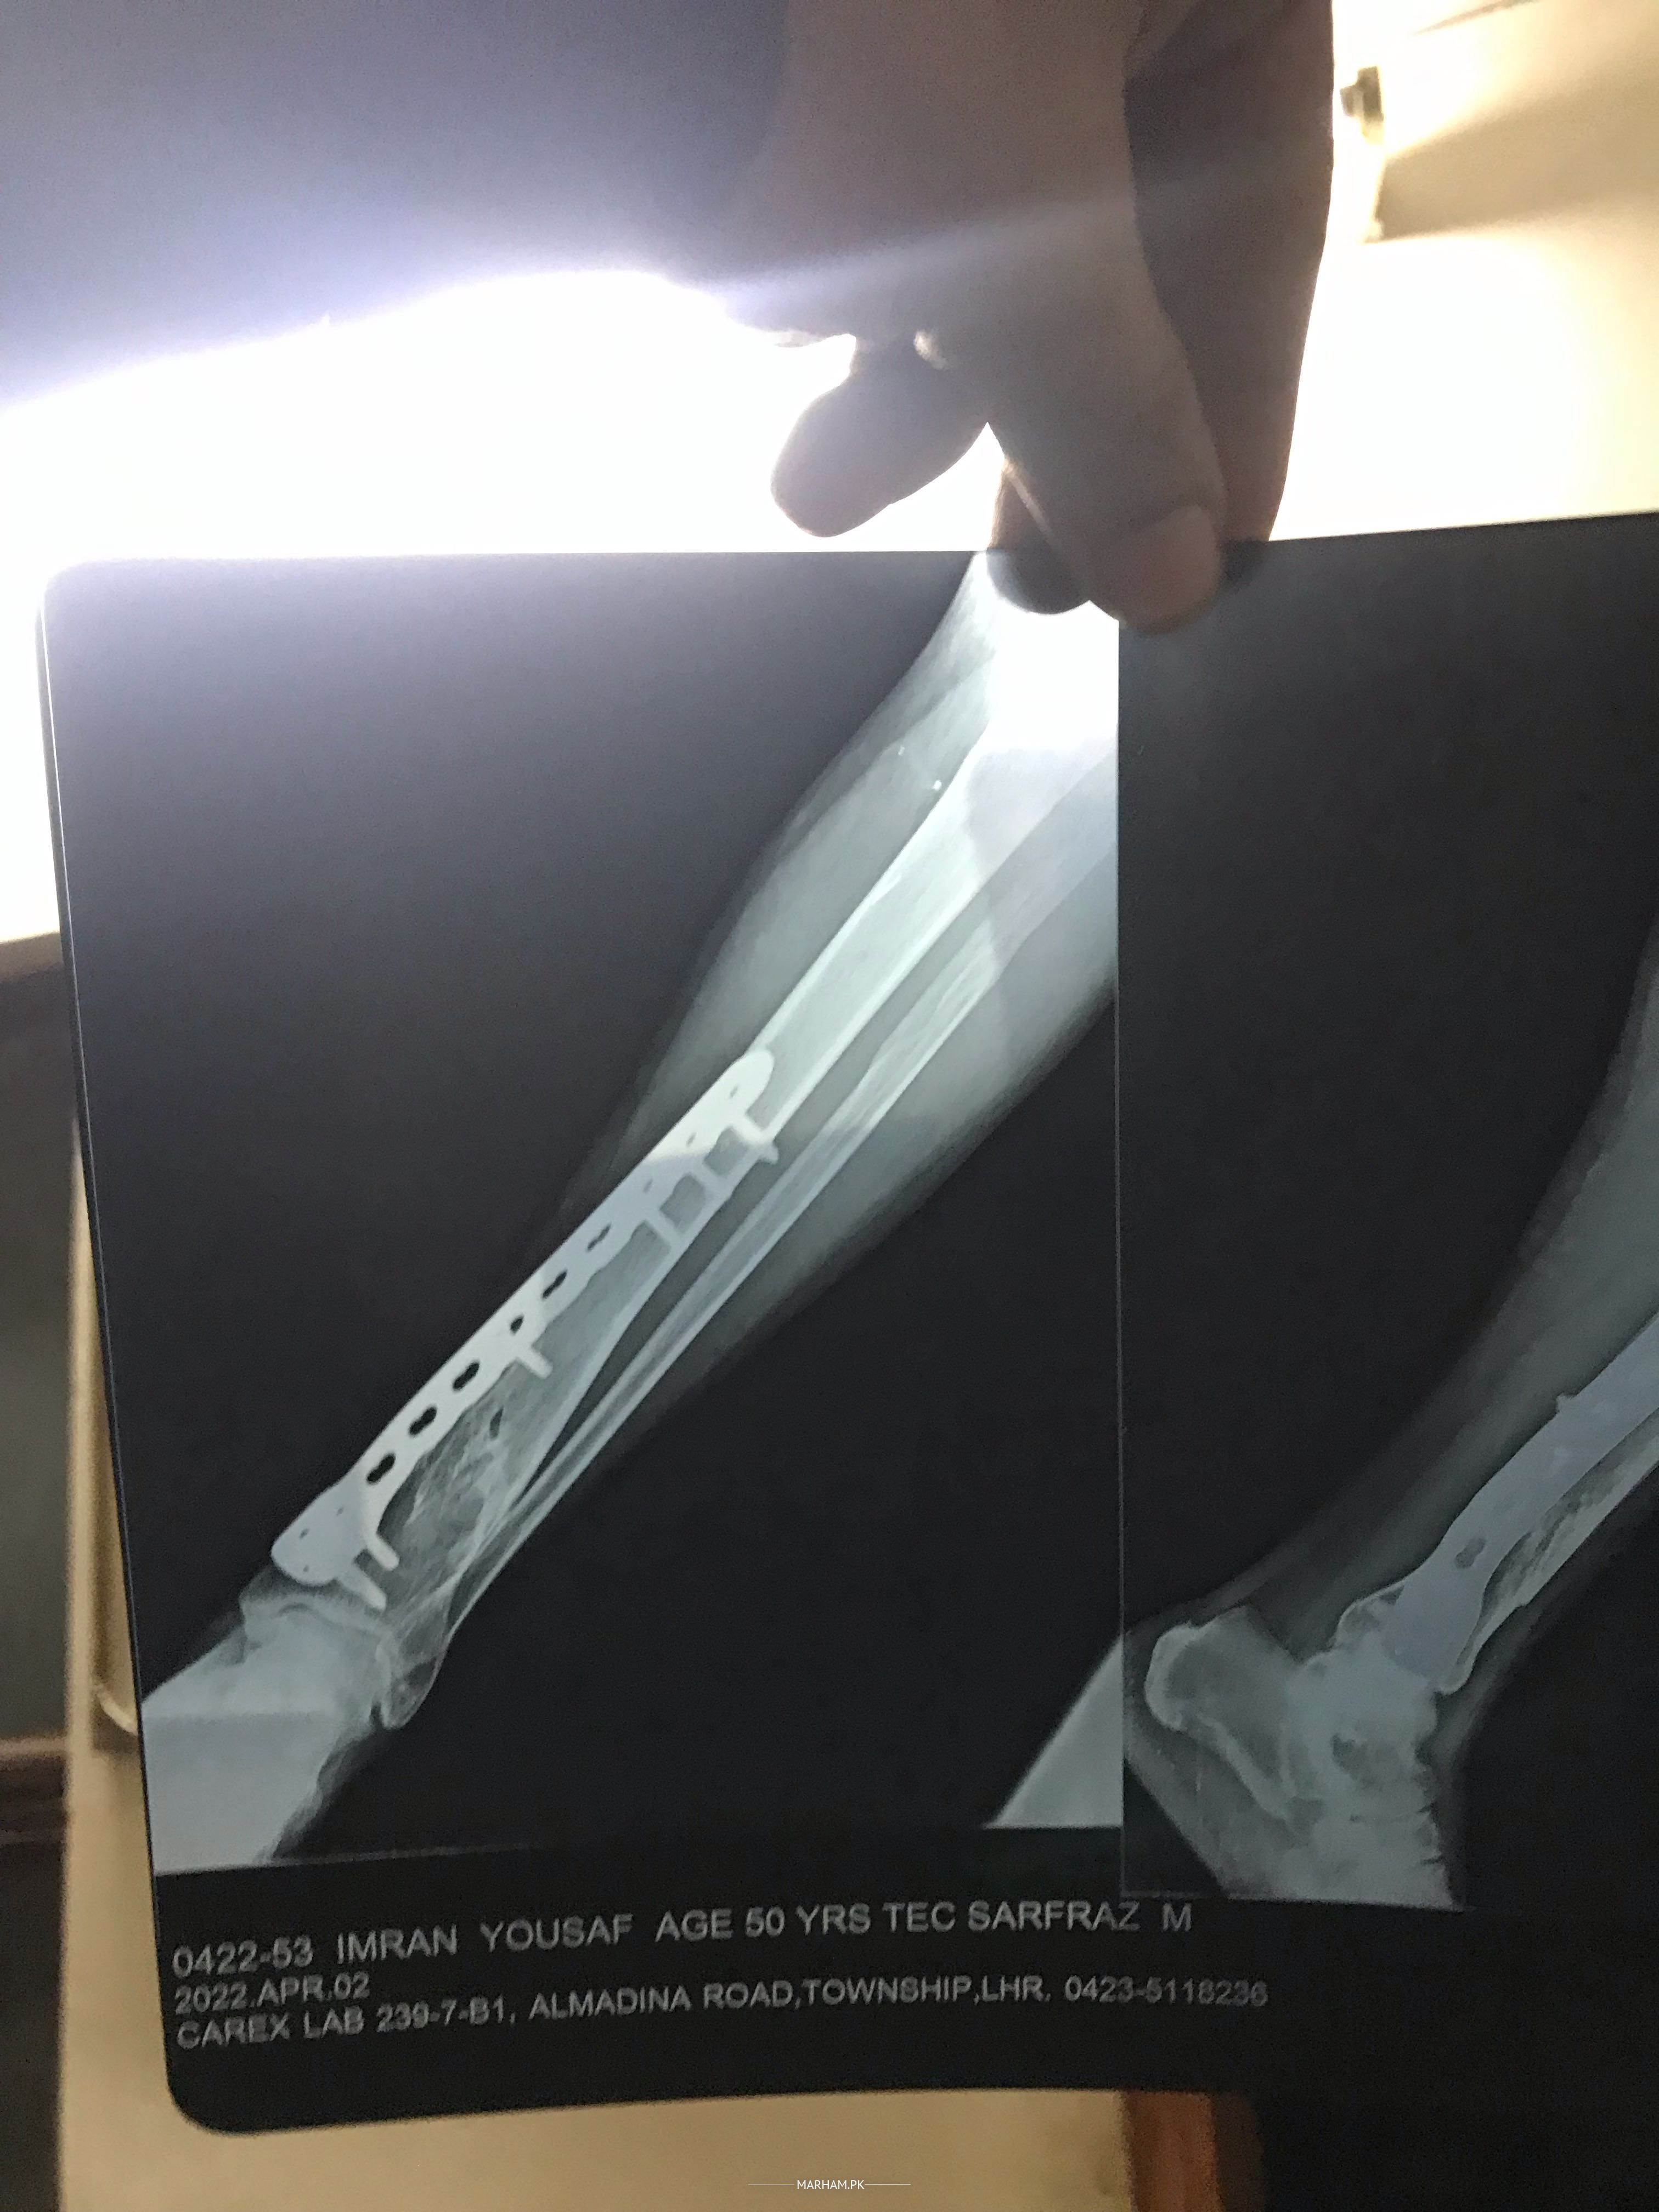

Assalamoalikum Father ki leg ma se plate nikalwai thi maximum 5 months pehle unki pain abhi taq nai gai unko plate nikalne k bad still pain ha pahle b pain thi jiski wjha se plate nikalwai thi plate nikalwane se pain kam hoi ha phle se laqin abhi b still pain ha or father ki health week ho gai ha Kuch suggest kr den Kindly koi medican ya kuch suggest kr den wo Dr k pass jane se bhut ghabraty Allah apko khush rakhy Shukrea Allah hafiz before and after pics and xray b opration se pehle ki or opration k bad ki plates lagne k bad ki b xray lgay ab plates nikal gai ha laqin pain nai ja ray xray clear ha plates nikalne k bad ka xray ki picture available nai wo dr kehty clear ha opration k bad drd chali jani chai laqin abhi taq drd nai gai

Apke father ke X-ray main ne dekain hai. Ye complex fracture ta. 2 bones ka fracture multiple jaga tah.. Unko numbness ya leg sun tu nahin hojate??

Wo dr k pass jane se bhut ghabraty hain hua ase tha phle unka operation 2014 ma glt ho gya tha then again opration hua tha ab plate nikali ha 1 year ho gya ha laqin pain ni ja rai please help kren wo doctor k pass jane se bhut ghabraty hain Dr sab

2014 ma unka opration glt hua tha phle dr na tang galat jor di thi then again opration hua tha still 9/10 sall se pain nai jati tang week b ho gai ha